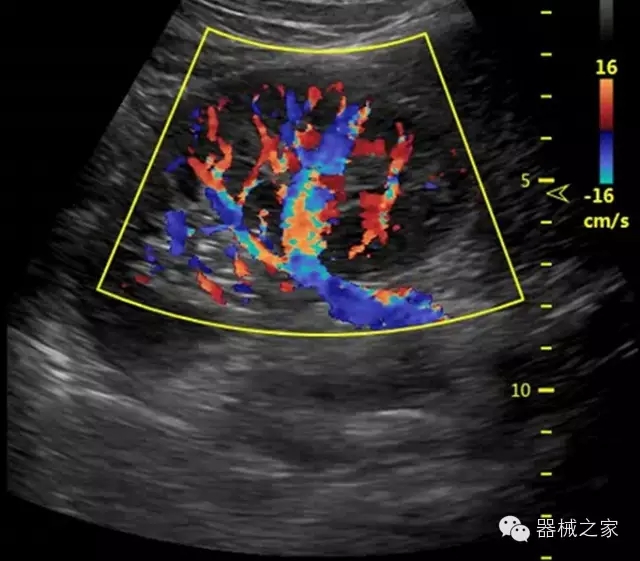

品牌:開立(SONOSCAPE)

公司簡介:

深圳開立生物醫(yī)療科技股份有限公司作為中國民族醫(yī)療產(chǎn)業(yè)的優(yōu)秀引導者,自成立伊始,一直致力于臨床醫(yī)療設備的研發(fā)和制造,產(chǎn)品涵蓋醫(yī)用數(shù)字超聲診斷系統(tǒng)、電子內(nèi)窺鏡系統(tǒng)、全自動五分類血液細胞分析儀以及自主研發(fā)的探頭群。

官方網(wǎng)站:www.sonoscape.com.cn

經(jīng)典產(chǎn)品:S8EXP

臨床圖片賞析

產(chǎn)品特點

優(yōu)異的成像技術

·亞陣元技術:獨有的亞陣元技術,對獨立晶片做二次切割,減少旁瓣偽像,增加臨床診斷的準確性;

·μ-Scan微米成像技術:開立獨有的μ-Scan技術,還原出真實細膩、層次對比優(yōu)異的二維圖像;

·倒相諧波成像技術:倒相諧波技術在去除基波信號的基礎上獲取兩倍二次諧波信號,提高組織圖像的對比分辨力;

·智能微血流成像技術:智能微血流捕捉技術可以提取出隱藏在背景噪聲中的弱血流信號,大大提高低速血流的敏感性;